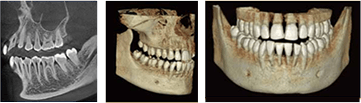

的確な診断、精細な診療のために

- デジタルパノラマレントゲン

- 従来と比べて放射線量が少なく、短時間で撮影できるため、患者様の負担を軽減することができます。また、正確な診断だけでなく、インプラント治療に欠かせないシュミレーションも行え、より安全な治療にも役立ちます。